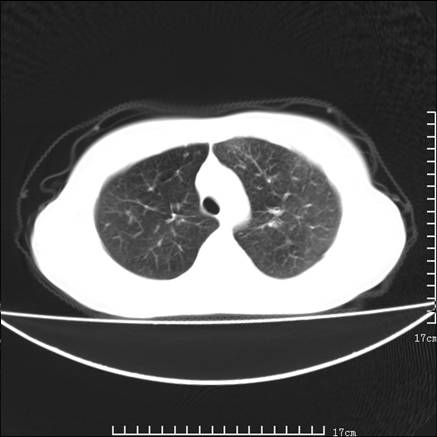

女,46岁,患胃溃疡多年,溃疡大小约1.0cm左右,后于5年前手术,病理为胃癌。主诉:半月前感冒后胸闷,气短,有咳嗽,无明显咳痰,无发热。偶有腰背部不适。

以下为高分辨扫描图像

双肺小叶间增厚,双肺散布粟米影和磨玻璃状影,以双肺上叶为重。结合病史考虑转移(癌性淋巴细管炎)可能性大。

结合病史:认为是典型肺部癌性淋巴管炎、淋巴结转移。请看图解。

正如caihe主任所言,影像表现结合临床病史应该支持肺癌性淋巴管炎;上肺大片边缘不清的渗出病变,多系感染所致,临床有感冒病史并咳嗽表现。肺癌性淋巴管炎临床一般无咳嗽、咳痰症状。

肺癌性淋巴管炎征象分为主要征象及合并征象,主要征象包括:

1、近肺门支气管血管周围间质结节状增厚;

2、小叶间隔结节状增厚;

3、小叶中央间质结节状增厚;

4、胸膜下间质结节状增厚。

合并征象为:纵隔淋巴结增大,胸腔积液,肺多发随机分布的小结节等。